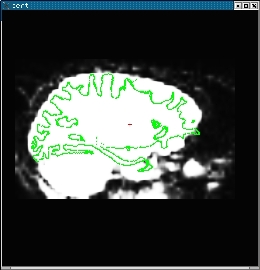

You will also see an anatomical similar to the one on the left below. Pressing the "COMPARE" button will allow you to flip between the anatomical (left) and functional (middle). The green line is the orig surface. It is the same in both the anatomical and functional. The right is the same image as the middle without the surface.

tkr-anat-sag-151-small.jpg tkr-func-sag-151-small.jpg tkr-func-sag-151-nosurf-small.jpg

The second step is to make sure there was not a left-right flip. This is tricky because the brain is very symmetrical. However, the cortical folding patterns often have subtle asymmetries. In general, you cannot see the folding patterns in the functional, but you can see the CSF which will also follow the surface (see the images above). Make sure that asymmetries in the (green) surface are present in the CSF.

The final step is to check the alignment. This is done by making sure that green surface follows the contour of the CSF.